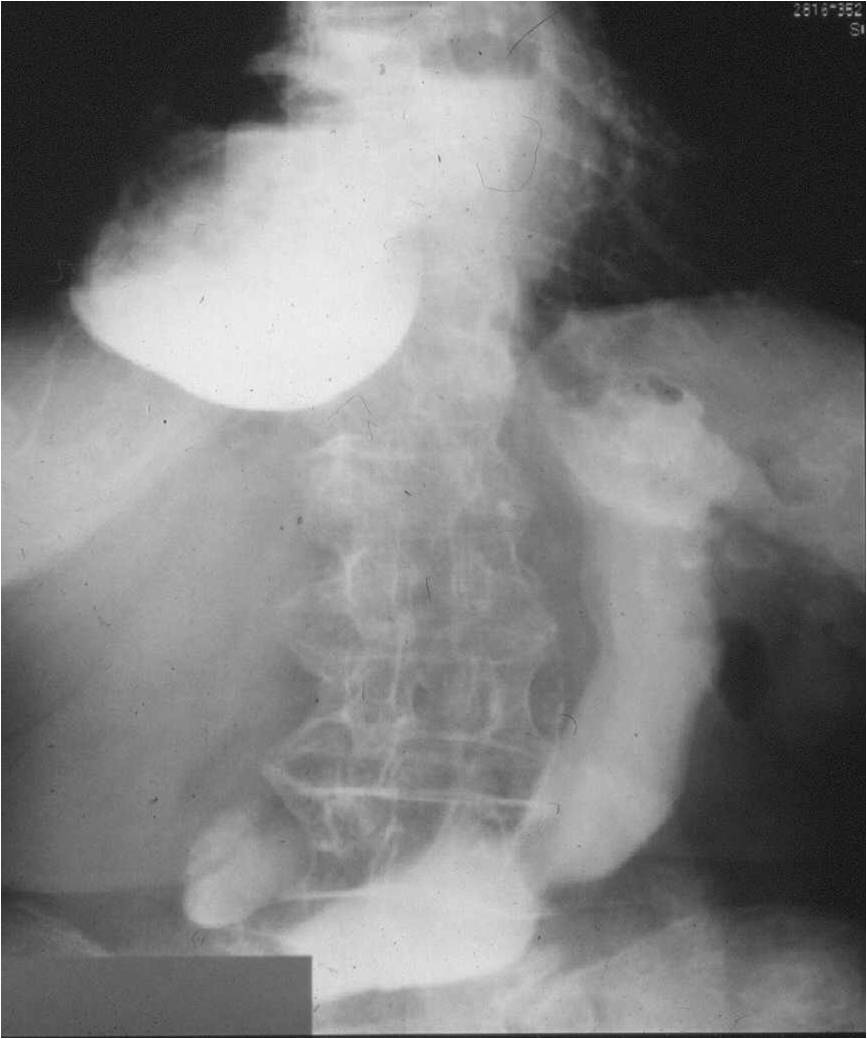

Image

Fig.2.: Achalasia

Radiographic findings: marked dilatation of the esophageal lumen. Luminal diameter can be seriously widened. In advanced cases the tortuous gullet constitutes the mediastinal interface. The cardia shows conical narrowing. The esophageal lumen is filled with undigested food. Opening of the cardia is delayed, emptying is intermittent. The stomach is shrunken. The result is a so called microgaster as the esophagus takes over the stomach’s reservoir function.